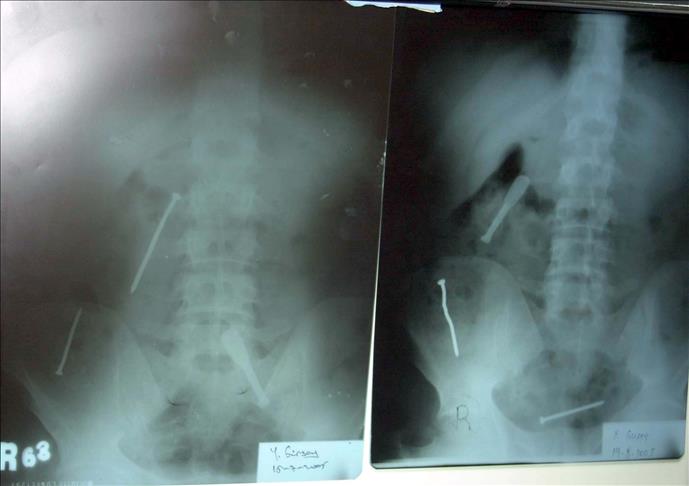

Harmankaya'nın yuttuğu çiviler, Kırıkkale Yüksek İhtisas Hastanesi'nde ameliyatla çıkarıldı.

Hastanenin başhekim yardımcısı ve genel cerrahi uzmanı Dr. Hüdaver Nurlu, ''Hastamızı akut karın zarı iltihabı teşhisiyle ameliyata aldık. Ameliyatta hastanın daha önce yuttuğu iki inşaat çivisinin yemek borusunu, mideyi ve ince bağırsağı geçip kalın bağırsağın girişine geldiğini, çivilerden birinin bağırsağı delip karın duvarına saplandığını gördük. Ameliyatta iki çiviyi bağırsaktan ve saplandığı karın duvarından çıkardık. Hastamızın durumu iyi. Taburcu etmeyi bekliyoruz'' diye konuştu.